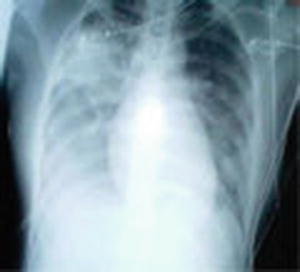

On an international level, the emergence of the severe acute respiratory syndrome (SARS) was certainly a time of uncertainty. Wenzel et al. describe how, in retrospect, the first human SARS victim was a traveler from an agricultural area of China in November 2002. The world began to suspect a problem 3 months later, when seven persons staying on the same floor in the same hotel in Hong Kong contracted the virus and carried it home to five different countries. By April, 2003 SARS, with a death rate of nearly 5 %, had been reported in 27 countries, as public health authorities, swimming in a sea of uncertainty, urgently sought to find the cause and a way to stop its spread [3] (see Fig. 9.8).

Fig. 9.8.

Chest X-ray of a patient with SARS. http://commons.wikimedia.org/wiki/File:SARS_xray.jpg

Just to extend the “swimming” metaphor a bit. The “water” also contains microorganisms, such as the human immunodeficiency virus Ebola virus, or Mycobacterium tuberculosis, to which health providers are not immune. Enter the water with care.